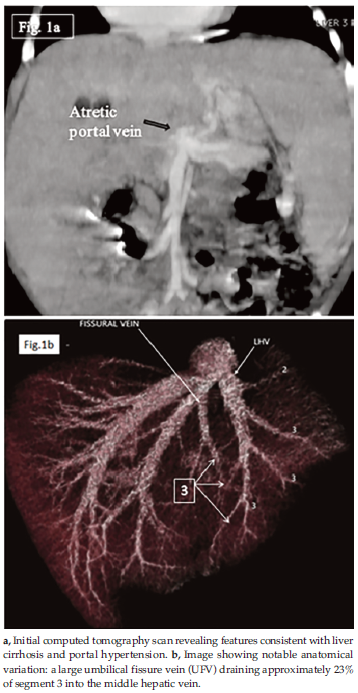

Initial evaluation showed bilirubin level of 11.9 mg/dL, albumin level of 2.0 mg/dL, and inter-national normalized ratio of 1.4. A computed tomography (CT) scan revealed features consistent with liver cirrhosis and portal hypertension, along with an atretic portal vein above the confluence of the superior mesenteric and splenic veins (Figure 1a). Despite receiving nutritional support in the weeks leading up to the surgery, she presented with severe malnourishment, weighing 5.5 kg and measuring 67 cm in height, which is a weight-for-height ratio below -3 standard deviations according to World Health Organization standards.

Although the segmental arterial and portal vein anatomy were standard, a notable anatomical variation was identified: a large UFV draining approximately 23% of S3 into the middle hepatic vein (MHV) (Figure 1b). Despite this variation, an S3 graft was selected over an S2 graft because of its more favorable estimated GRWR.

Figure 1. Atretic Portal Vein in an Infant With Cirrhosis and Donor Umbilical Fissure Vein Variant